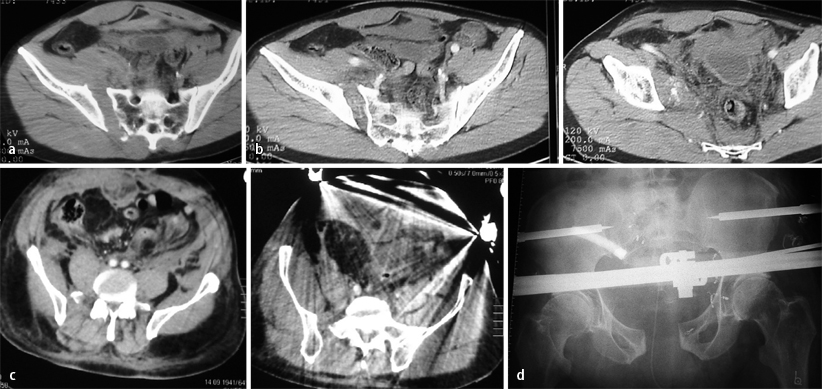

Fall 1, 32-jährige Patientin, AO-Fraktur 61B2.1., a a.-p. Beckenübersichtsaufnahme, b CT: Kompressionsfraktur der rechtsseitigen Massa lateralis, c a.-p. Beckenübersichtsaufnahme postoperativ, d,e Beckenübersichts- und Inlet-Aufnahme nach Entfernung des Fixateurs und Vollmobilisation, weitere Erläuterungen s. Kasuistik

Fall 4, 62-Jähriger mit AO-Verletzung 61C1.2, a,b Kontrastmittel-CT: Nachweis einer erheblichen aktiven Blutung extraperitoneal, c,d Kontrastmittel-CT: Nachweis der trotz Beckenzwinge und Fixateur-externe-Anlage persistierenden Blutung, Embolisation der aktiv blutenden A.-iliaca-interna-Äste, weitere Erläuterungen s. Kasuistik

Fall 1

Die 32-jährige Patientin war im europäischen Ausland gestürzt und nach Vorlage der a.-p. Beckenübersichtsaufnahme (Abb. 1 a) mit „stabiler“ isolierter vorderer Beckenringfraktur unter starken Beschwerden voll mobilisiert worden. Die rechtsseitige Sakrumfraktur wurde erst 10 Tage nach dem Trauma und der Rückkehr in die Heimat diagnostiziert (Abb. 1 b).

Die Fraktur wurde reponiert und mittels supraazetabulärem Fixateur externe und transiliosakraler Stellschraube stabilisiert (Abb. 1 c). In Abb. 1 d,e sind die Beckenübersichts- und Inlet-Aufnahme nach Entfernung des Fixateurs und Vollmobilisation dargestellt.

Fall 4

Bei dem 62 Jahre alten männlichen Patient mit einer AO-Fraktur 61C1.2 wurde mittels Kontrastmittel-CT eine erhebliche aktive Blutung im Extraperitonealraum nachgewiesen, die trotz Beckenzwinge und Anlage eines supraazetabulären Fixateur externe persistierte. Bei der somit erforderlichen operativen Versorgung wurden die aktiv blutenden Äste der A. iliaca interna („coiling“) embolisiert (Abb. 4) und eine innere Osteosynthese vorgenommen.